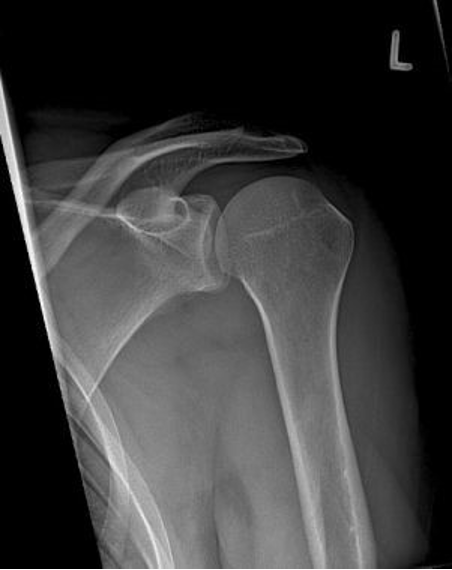

Bij dit letsel zit de kop (= onderdeel is van het bovenarmsbot), niet meer in zijn kom (= onderdeel van het schouderblad), waarbij het kapsel van de schouder overrekt is geraakt. Dit ontstaat meestal door een val op de arm of hand, waarbij tevens de schouder naar buiten is gedraaid. De kop schiet er meestal aan de voorkant uit, maar dat kan ook naar achteren of naar onderen gebeuren.

Vaak wordt er bij het lichamelijk onderzoek al een afwijkende stand van de schouder gezien. Op de aanvullende Röntgenfoto is meestal wel goed te zien dat de schouder uit de kom is. Soms gaat het uit de kom zijn gepaard met een breukje van de schouderkop of kom.